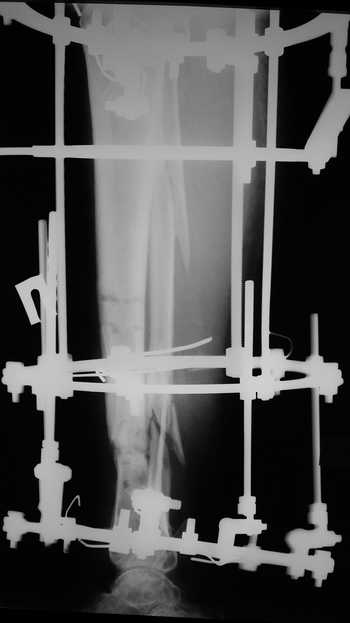

Еще один пример.

Мужчина, 33 года, резекция б\б кости по поводу остеомиелита после открытого перелома. Стандартная методика билокального остеосинтеза (рис 1 и 2). В конце удлинения выявилось неудовлетворительное взиморасположение перемещенного фрагмента и дистального отломка (рис 3). Планирование (рис 4).

Адаптация отломков гексаподом за 5 дней (рис 5). Замена гексапода на обычные штанги (рис 6 и 7)